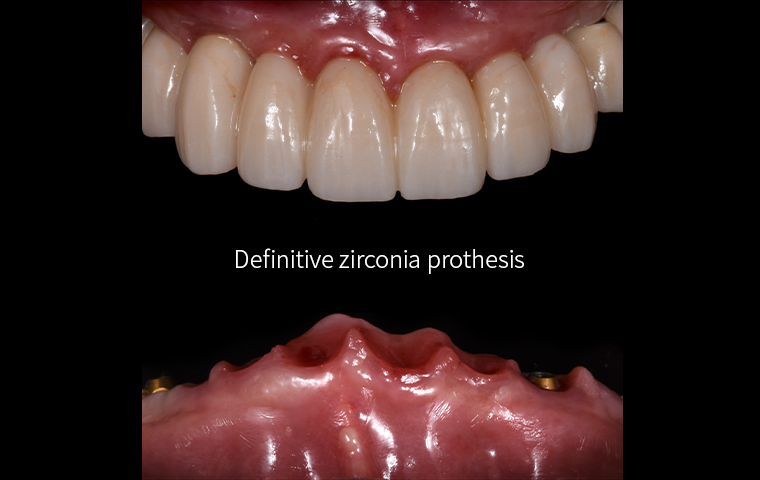

All-on-X

Practical Digital Prosthodontics: Understanding and applying

All-on-X treatment concept

Dr. Janghyun Paek

Professor at Kyunghee University, Department of Prosthodontics

All-on-X

Practical Digital Prosthodontics: Understanding and applying

All-on-X treatment concept

Dr. Janghyun Paek

Professor at Kyunghee University, Department of Prosthodontics

| 13:30 – 14:30 |

All-on-X

Dr. Janghyun Paek

|

Practical Digital Prosthodontics: Understanding and Applying All-on-X Treatment Concept |

| 13:30 – 14:30 |

All-on-X

Dr. Janghyun Paek

|

Practical Digital Prosthodontics: Understanding and Applying All-on-X Treatment Concept |

Special Pre-Day Course

Practical Digital Minimalism

Dr. Janghyun Paek

Explore the digital implant dentistry, including the All-on-X treatment concept, guide surgery, immediate loading protocols, prosthodontic considerations, and soft tissue contouring. Course also includes hands-on for All-on-X implant placement, prosthodontic components, intraoral scan, and immediate loading.

Explore the digital implant dentistry, including the All-on-X treatment concept, guide surgery, immediate loading protocols, prosthodontic considerations, and soft tissue contouring. Course also includes hands-on for All-on-X implant placement, prosthodontic components, intraoral scan, and immediate loading.